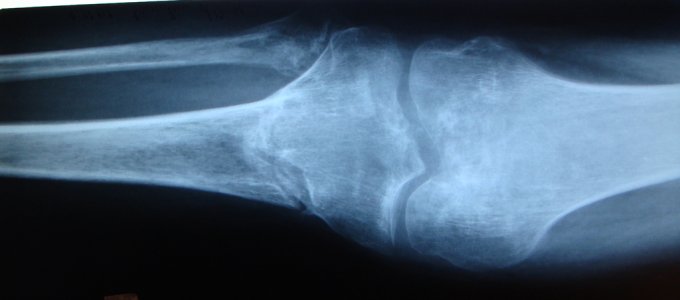

Здравствуйте доктор, 01.05.2008 года получил закрытый оскольчатый внутрисуставной чрезмыщелковый перелом костей левой голени со смещением отломков. Лечили консервативно - скелетным вытяжением. 06.06.2008 г., наложено повязку из полимерных бинтов от кончиков пальцев левой стопы до в/3 левого бедра. Проходил до 06.11.2008г. в гипсе. После было рекомендовано ходить с палочкой, Но боли не проходили и 24.12.2008 г. были сделаны дополнительные снимки из которых было видно смещение кости. Было рекомендовано, на месяц, зафиксировать ногу с помощью ортеза, что я и сделал. Доктор подскажите пожалуйста что необходимо для скорейшего срощения такого перелома (диета, припораты выробатывающие кальций?). Подскажите, глядя на последние снимки, есть ли там образование ложного сустава. Фото снимков прикреплены, название файла соответствует дате снимка. Большое спасибо, с уважением Алексей.